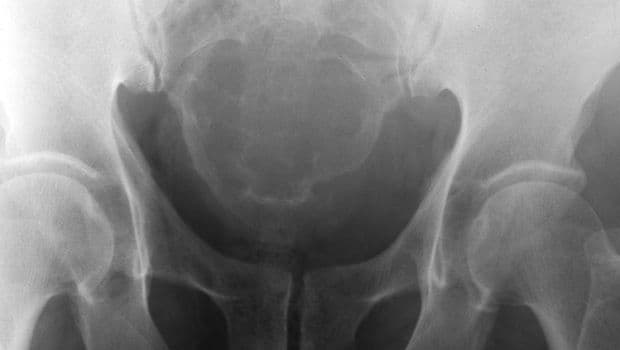

#Csont#daganat#jóindulatú#kóros szövetburjánzásCsontdaganatok@brekkszii•2011. szept. 25.•1 perc olvasás